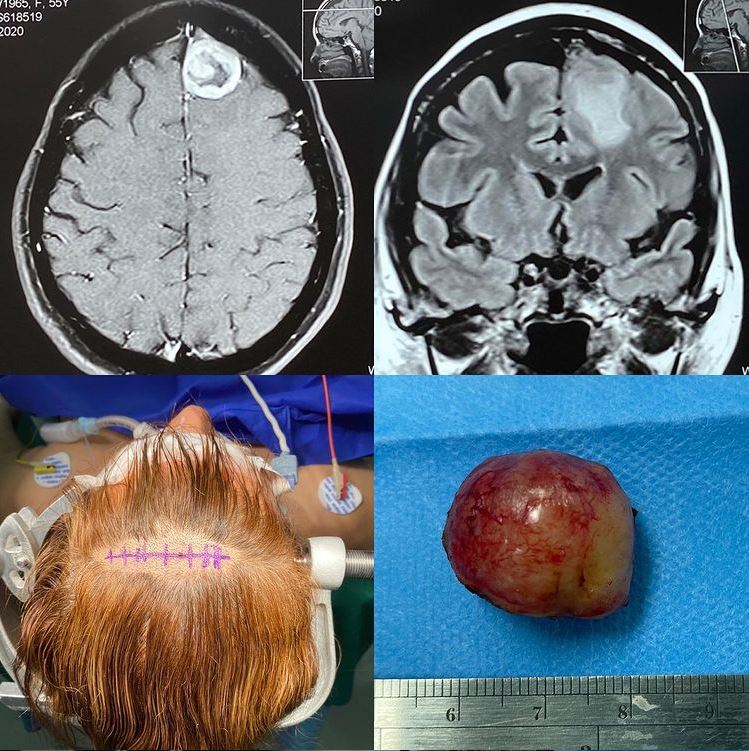

Resección de Meningioma